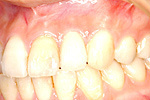

症例 14

① 前歯1本が無い状態です。通常は前後の2本の歯を削ってブリッジにしますが、インプラントをすることにより、健康な歯を削る必要はなくなります。

② インプラントが埋め込まれて安定した状態です。

③ インプラントに固定式の歯が入ったところです。健康な自分の歯を守る事ができました。

20才代 女性

総額:42万円(税別)

リスク副作用:顎骨の変化により、自分の歯との間に隙間や段差が生じることがあります。